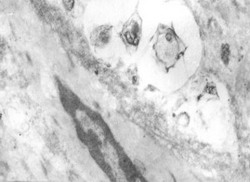

Рис. 4. Фагоцитированные микробы в отечной жидкости в подслизистом слое с дезорганизацией клеток. Во время начала ишемии-реперфузии. Электронограмма (х8000)

Другая морфологическая картина была получена при исследовании ткани кишечника, когда после реперфузии (во время запрограммированной релапаротомии) приходилось ререзецировать кишечник. В частности, в начале реперфузии в слизистом слое выявляется геморрагическая инфильтрация, дезорганизация и некробиоз ворсинок кишечника.

Эпителиальные клетки вздуты, нарушена их поверхность вследствие шелушения некоторых из них, местами – разрывы клеточных мембран с выделением клеточных органелл. В мышечном слое на фоне выраженного отека и диссоциации межклеточных соединений встречаются транслокации кишечных бактерий(рис. 4).